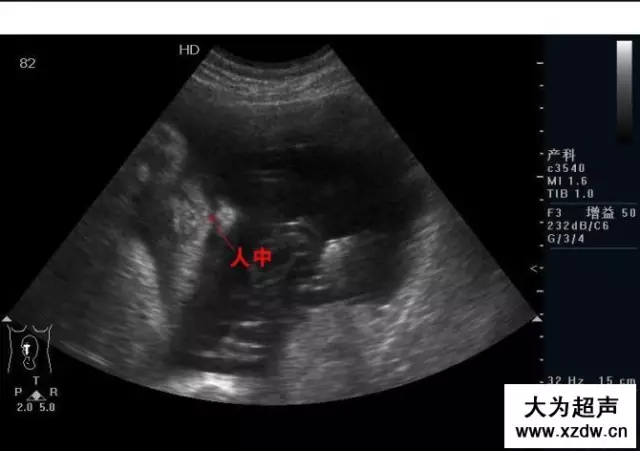

產科超聲正常圖片